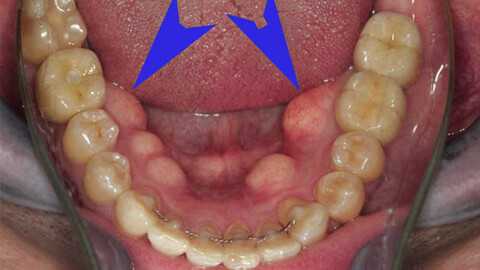

Как правило, остеофиты небольших размеров не вызывают никаких жалоб. Костные наросты могут быть выявлены во время определения степени атрофии кости, оценки уровня податливости слизистой оболочки на подготовительном этапе перед протезированием. Наиболее часто экзостозы челюсти локализуются в зоне срединного небного шва, а также с оральной стороны альвеолярного отростка в проекции нижних премоляров. Открывание рта у пациентов с экзостозом челюсти свободное, осуществляется в полном объеме. Слизистая над остеофитами бледно-розовая, без видимых патологических изменений, подвижная.

При увеличении костных выступов слизистая истончается, вследствие чего возрастают риски ее травматизации базисом протеза или острыми краями разрушенных стенок зубов. При пальпации экзостозы челюсти представляют собой плотные образования с бугристой или гладкой поверхностью, не спаянные с окружающими мягкими тканями. Располагаясь в области суставного отростка, экзостоз челюсти вызывает болевые ощущения. При этом наблюдается ограничение при открывании рта, смещение ментального отдела в здоровую сторону, нарушение окклюзии. Регионарные лимфоузлы не пальпируются. Общее состояние у пациентов с экзостозом челюсти не нарушено.